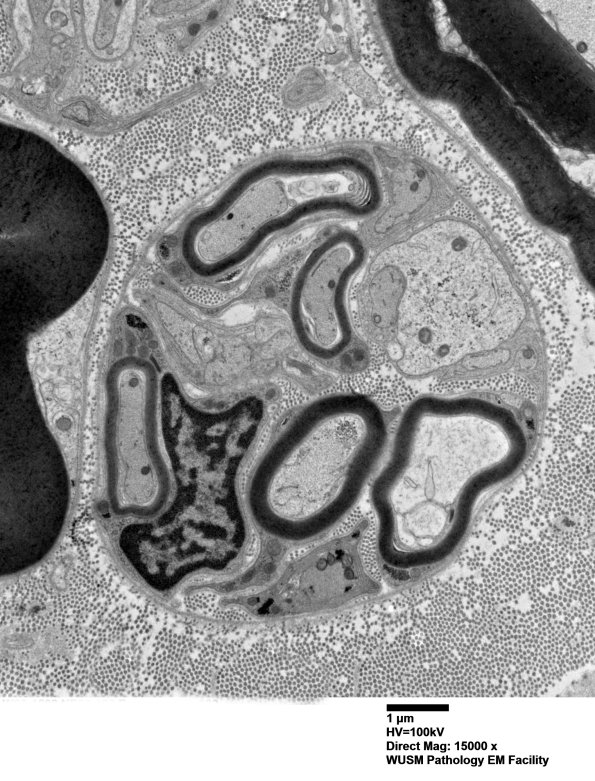

2B3-6 Multiple images of this cluster of immature, likely regenerative axons, collections of Schwann cell cytoplasm and small axons which represents pathologic alteration and not normal structures. Notice the intact basal lamina which surrounds the entire collection of elements. (Electron micrographs)